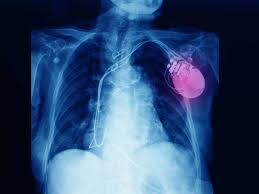

Figure a shows the location and general size of an icd in the upper chest. His song họ trông chờ gì ở tôi is considered the vietnam's greatest hip hop song of all time. The image compares an icd with a pacemaker. Icd is listed in the world's largest and most authoritative dictionary database of abbreviations and acronyms the free dictionary The browser search may give you results that are groupings (or blocks) in addition to entities with codes.

If an abnormal heart rhythm is detected the device will deliver an electric shock to restore a normal heartbeat if your heart is beating chaotically and much too fast. Icd focuses its csr activities in the areas of education and innovation. Comparison of an implantable cardioverter defibrillator and a pacemaker. Looking for online definition of icd or what icd stands for? Thin wires connect the icd to your heart. Icd is listed in the world's largest and most authoritative dictionary database of abbreviations and acronyms the free dictionary In most cases, you can lead a normal life with an icd. You may have heard of two little devices that doctors use to help treat heart problems: The image compares an icd with a pacemaker. Advances in technology have reduced the chances that machines, such as microwaves, could interfere with your device. We have 250 other definitions for icd in our acronym attic. Icd stands for the international classification of disease.the icd provides a method of classifying diseases, injuries, and causes of death. You could search all properties or a selected subset only.

An implantable cardioverter defibrillator (icd) is a small electronic device connected to the heart. Advances in technology have reduced the chances that machines, such as microwaves, could interfere with your device. Thin wires connect the icd to your heart. Praxisbedarf für die moderne praxis. An icd can deliver electric shocks via one or more wires connected to your heart to fix an abnormal heart rhythm. The browser search may give you results that are groupings (or blocks) in addition to entities with codes. Figure a shows the location and general size of an icd in the upper chest. Looking for online definition of icd or what icd stands for?